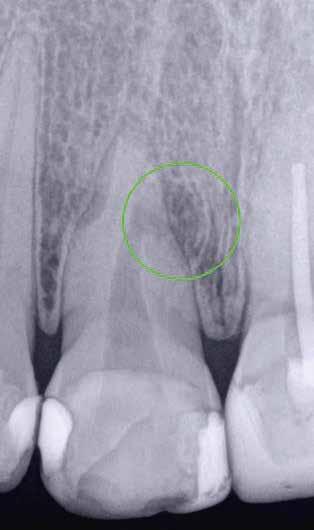

1. a–f ábrák: A cingulumon keresztül gömbfúróval kialakított hozzáférés a trepanációs kavitás labiális irányba történő túlzott mértékű kiterjesztését eredményezheti, és ez lényegesen növelheti a perforáció esélyét (a). A guttapercha átsejlik a lágyrészek alatt (b). Klinikailag igazolt perforáció (c). A preoperatív sagittális irányú CBCT-szeleten jól látható a labiális perforáció (d). Labiális irányú perforáció (fekete nyíl; e). A tényleges gyökércsatorna (piros nyíl; f).

2. a-b ábrák: A cingulumon keresztül gömbfúróval végzett trepanálás túlzott pericervikális dentin áldozattal, fordított tölcsér effektussal és perforációk kialakulásával járhat (fehér nyíl).

1a 1b 1c 2a 2b 1d 1e 1f

A frontfogakban történő hozzáférési nyílás kialakítása

A frontfogakban a hozzáférési nyílás kialakítását hagyományosan a fogak linguális vagy palatinális felszínén, a cingulumon keresztül egy gömbfúró segítségével kezdjük. A linguálisan elhelyezkedő kiemelkedés teljes eltávolítása, továbbá a pulpaszarvak teljes feltárása egy háromszög alakú hozzáférési nyílást eredményez. 7 Ezt a módszert a fogak esztétikai megjelenésének megőrzése érdekében fejlesztették ki. Ez azonban időnként a saját foganyag indokolatlan eltávolításával, a trepanációs kavitás labiális irányba történő túlzott kiterjesztésével, perforációval, valamint a fog kritikus helyen, a pericervikális dentin (PCD) területén történő meggyengítésével jár (1. a–f és 2. a-b ábrák). 19 Felmerült, hogy a pericervikális dentin rendkívül fontos szerepet játszik a rágóerő gyökerek irányába történő továbbításában, és elképzelhető, hogy a gyökérkezelt fogak hosszú távú megtartása szempontjából a legfontosabb tényező az ép pericervikális dentin megőrzése lehet. 20 A cingulumon keresztül történő hozzáférési nyílás

kialakítása során fennáll a fog labiális irányú perforációjának veszélye, mivel ilyenkor a foganyag elvételét labiális irányú fúrótartással kezdjük. Nemrégiben újragondolták a